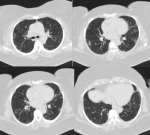

Case 3: was admitted on account of cough and difficulty in breathing of 3 days duration, initially exertional but later present at rest. He had no fever or chest pain. He was hypoxaemic and nursed in prone position with minimal improvements in the oxygen saturation. Arterial blood gasses showed respiratory alkalosis with compensatory metabolic acidosis. CRP and D-dimer were elevated. He had a CT pulmonary angiogram to visualize the lungs and rule out a pulmonary embolism. This showed bilateral alveolar consolidation with pan-lobar affectation, with typical radiological findings of adult respiratory distress syndrome (ARDS) Figure 3. Nasopharyngeal swab taken for RT-PCR testing for COVID-19 was positive. He was placed on mechanical ventilation and had no clinical improvement until his death less than 24 hours after (Figure 3). Computed tomography images of case 3 on 3rd day of onset of symptoms showing bilateral lung consolidation (white lung) with a pan-lobar affectation and air-bronchograms. Peripheral ground-glass opacification in the left upper lobe. No evidence of pulmonary embolism was seen.

Cases 2 and 4, with difficulty in breathing had oxygen saturations of 90% or less despite oxygen supplementation and this improved moderately on nursing prone. In index case 3, the clinical condition worsened and progressed to death despite mechanical ventilation. Hypoxaemia is reported to provide a robust risk factor for fatal outcomes and is associated with death in patients with COVID-19-associated pneumonia independently of age and sex [7]. It is also associated with higher neutrophil counts, D-dimer and CRP levels as well as acute inflammation of the respiratory system, caused by respiratory virus or secondary bacterial infection [7]. CRP and D-dimer were elevated in the more severe 3 of our index cases, also consistent with a moderate to severe inflammatory process [8]. Imaging for COVID-19 pneumonia mainly comprises chest radiography and computed tomography (CT). Our patients underwent X-rays and computed tomography scans. Chest radiographs are an initial and quick method of evaluating for significant lung abnormality. They may be less sensitive than CT, but are widely available, cost-effective and are suitable for primary hospitals which do not have CT machines as well as for the bedside examination of critically ill patients. Where there is high clinical suspicion of COVID-19, it is possible that a positive CXR may obviate the need for a CT [9]. Up to 89% of X-rays in COVID-19 may be interpreted as normal or mildly abnormal [10]. This is similar to findings in our patients as the x-ray in case 1 was normal while the chest X-ray in case 2 showed ill-defined bilateral alveolar consolidation with a peripheral and lower lobe distribution. It also excluded other pathology such as pneumothorax or pleural effusion. The other two cases did not have chest X-rays.

CT is the gold-standard for detecting the presence of lesions in the lungs, especially high-resolution CT, as it has no overlapping structural interference and can detect small lesions. It is useful for the diagnosis and differential diagnosis of COVID-19, monitoring treatment outcomes and early detection of other complications [3]. In the early stage, it shows multiple small patchy ground glass and interstitial changes, then develops into multiple ground glass shadows and infiltration with a peripheral distribution [3, 8], similar to the changes seen in our index cases 2 and 4. Ground-glass opacification is a slightly higher density, usually-rounded and blurred lesion in the lungs, where the pulmonary blood vessels are visible [1]. The ground-glass and/or consolidative opacities are usually bilateral, peripheral, and basal in distribution [1, 11]. This may be explained by viral invasion and replication in the bronchioles and alveolar epithelium causing inflammation and thickening of the alveolar wall with a distribution mainly around the lung and under the pleura [3]. In more severe cases, pulmonary consolidation may occur. Consolidation may be related to acute diffuse alveolar injury, including oedema, red blood cells and cellulose deposition. Thickening of the pulmonary interstitium or fibrosis may also be seen as stripes [3]. Pleural effusion and pneumothorax are rare [4]. Our cases run the gamut from mild to moderate to severe. Case 1 was a mild type with mild clinical symptoms and imaging findings showed no features of pneumonia. The chest CT manifestations of COVID-19 often presented patchy ground-glass opacities or mixed ground-glass opacities and consolidation, predominantly involving the periphery of both lungs, that can change rapidly [8]. Li et al. in a multicentre study in China showed that some patients with normal chest CT imaging could test positive for COVID-19 [8]. Cases 2 and 4 were of moderate severity with fever, cough, hypoxia and bilateral peripheral infiltrates, predominantly in the lower lobe in case 2. These findings are consistent with the findings described in other studies as the disease progresses [3, 8].

Case 3 was in the severe stage with shortness of breath and hypoxemia with typical radiological findings of ARDS, requiring mechanical ventilation with no relief until his death. As inflammation progresses, there is extensive involvement of alveoli, followed by consolidation. With a strong reaction to an inflammatory storm, large exudation occurs in the alveoli of both lungs, showing a white lung appearance [3, 11], as in the index case 3. Air bronchograms, also present in this patient, are the low-density shadowing of air-containing bronchus in the consolidation of lung tissue. This results from pathogenic invasion of the epithelial cells, causing inflammatory thickening and swelling of the bronchial wall without obstructing the bronchioles [3]. Other computed tomography features which have been documented in COVID-19 patients, but not seen in our index cases include paving stones sign, fibrosis, traction bronchiectasis, vascular thickening, halo or reverse halo signs [3].

Figure 3: computed tomography images of case 3 on the 3rd day of onset of symptoms showing bilateral lung consolidation (white lung) with a pan-lobar affectation and air-bronchograms; peripheral ground-glass opacification in the left upper lobe; no evidence of pulmonary embolism was seen